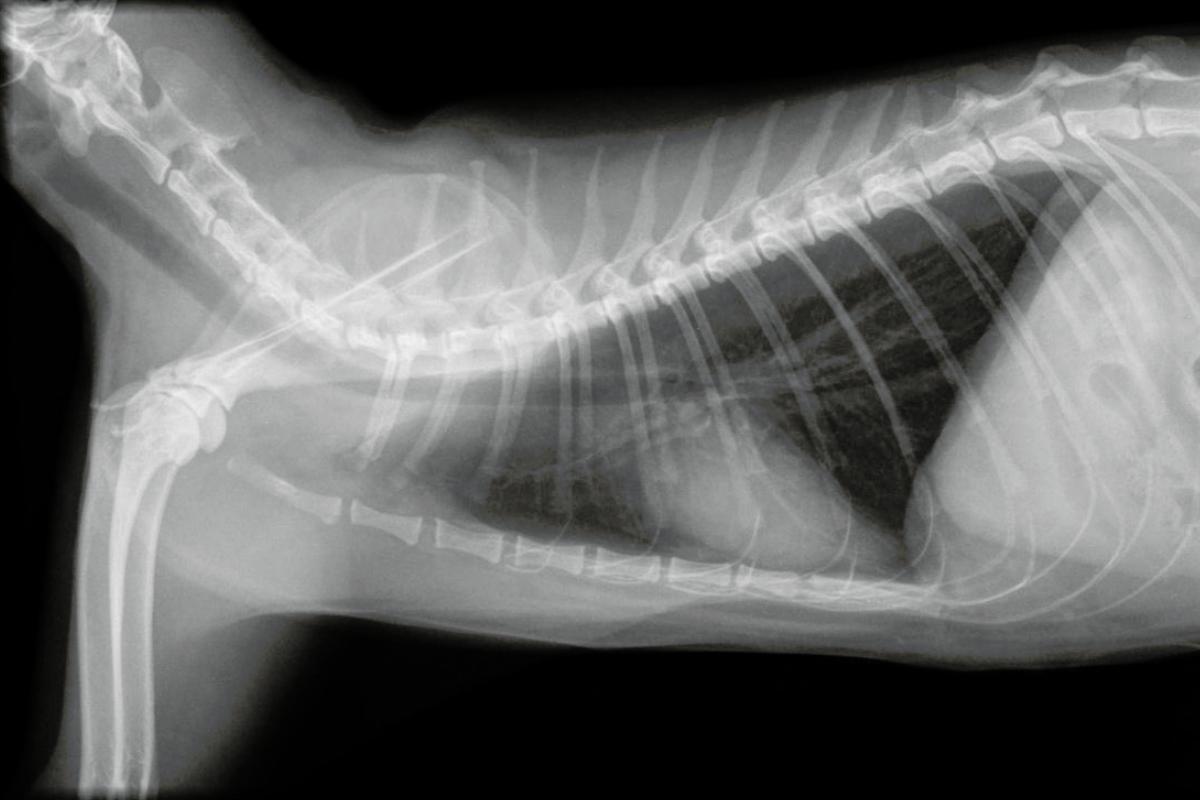

Ante síntomas como dificultad respiratoria, taquipnea y reducción de los sonidos pulmonares, el diagnóstico de derrame pleural es muy probable. En una radiografía se puede evidenciar presencia de líquido en el espacio pleural al impedir una visualización normal de los pulmones y con la ecografía se puede sospechar o deducir que tipo de líquido es (trasudado, sangre, linfa, pus), obteniendo clara la información con el análisis del líquido tras una toracocentesis mediante recuento celular, citología y bioquímica. En caso de sospecha de infección, el líquido se debe cultivar.